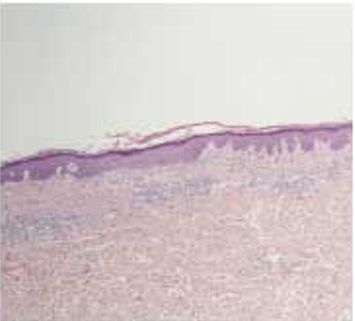

| Гистология |

|